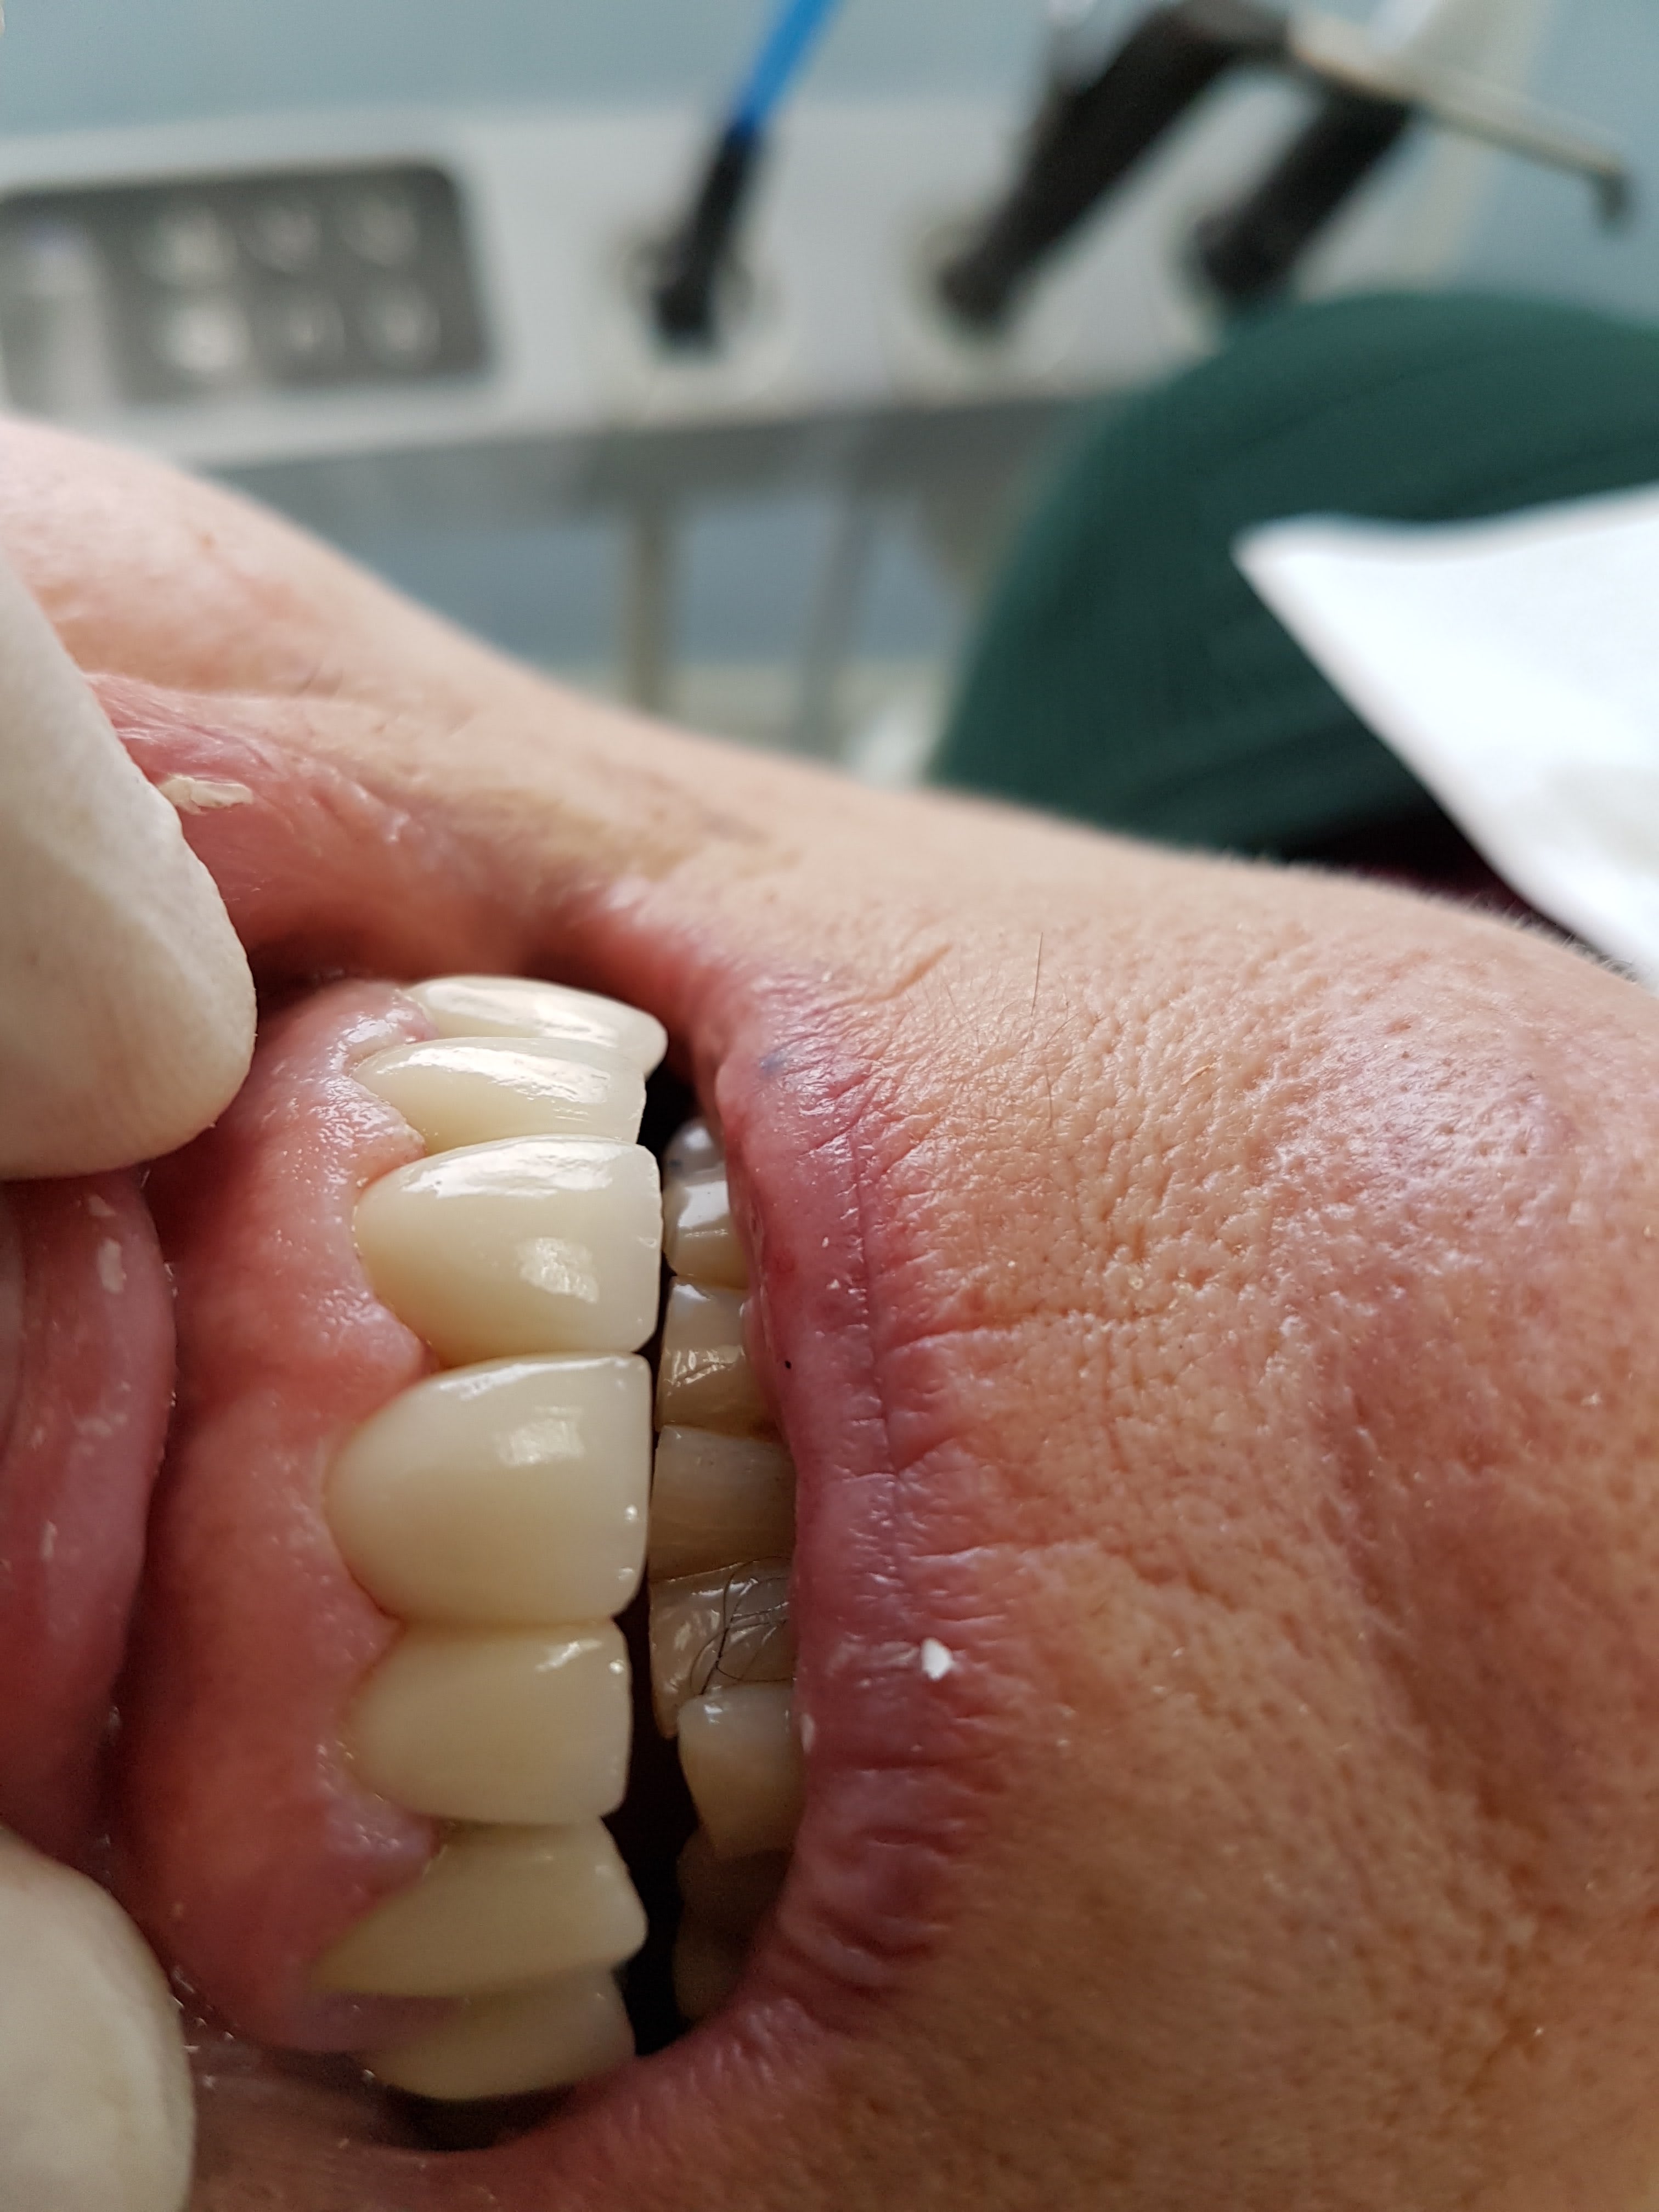

Pts de contacts OK, occlusion ok, adaptation inlay core oK. C'est l'essentiel.

Anatomie moyenne, mais comme le font aussi bien certains labos francais.

Tu t'en branles de la teinte en postérieur. C'est peut etre moi qui ne suis gourré. -)))

Mise en place nickel pas de retouches basta. 60 euros de moins que le protho habituel. mais là n'est pas l'important. Un peu plus et je pourrais faire mon endio molaire gratuite sans que ca change quoique ce soit pour moi. C'est ca qui est lamentable.